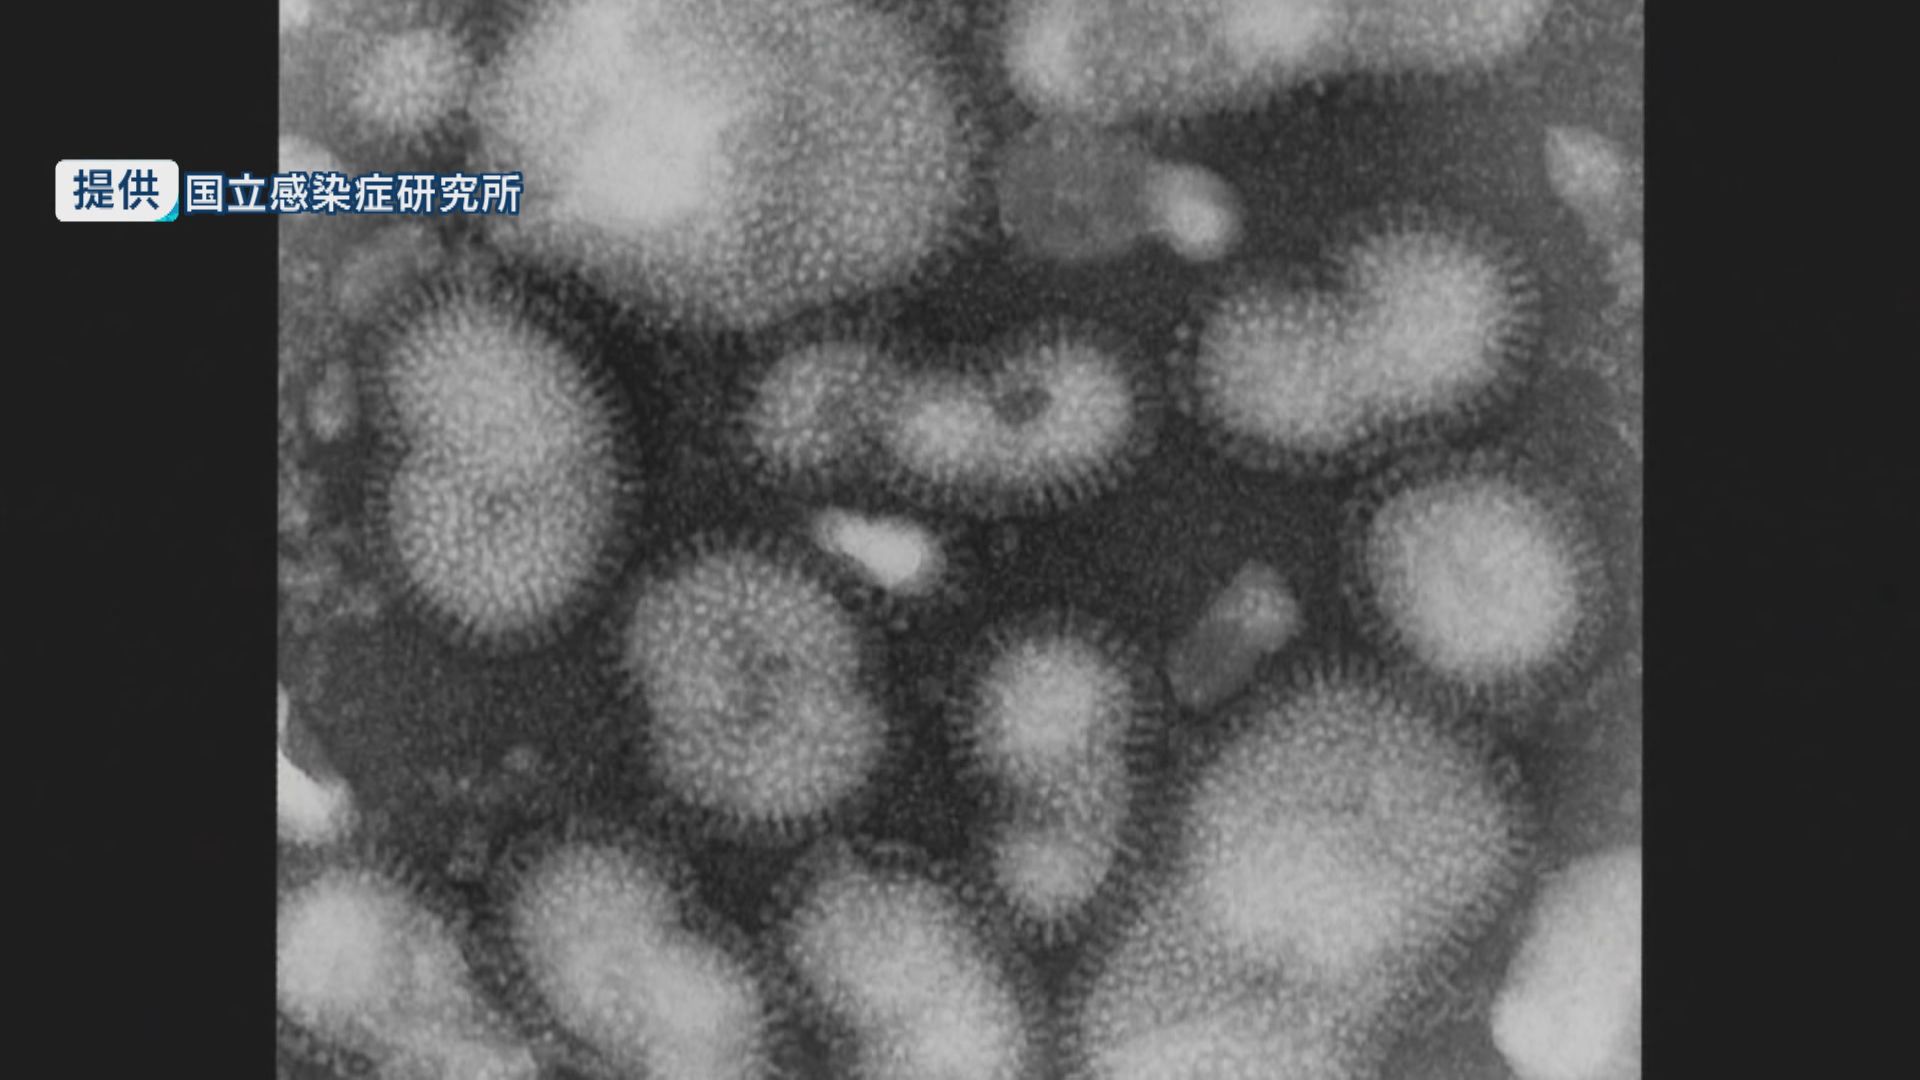

インフルエンザの感染者が増えていて、引き続き警報レベルとなっています。

県感染症情報センターによりますと、12月14日までの1週間でインフルエンザに感染した人は前の週よりも575人多い3060人でした。

定点当たりの報告数は「60.00」で、4週続けて警報レベルとなっています。